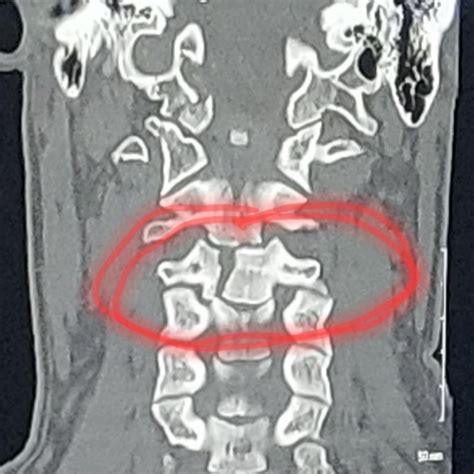

• Imaging Studies: Imaging studies, such as MRI, CT scans, and X-rays, provide valuable insights into a patient's health status. Clinical correlation helps radiologists and other healthcare providers interpret these images more accurately by comparing them with other clinical data.